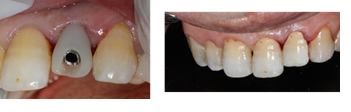

A 54-year-old female patient in good general health visited the outpatient department of the University Hospital Clinic of Odontology in Monastir, Tunisia, for therapeutic management of her left maxillary lateral incisor.Endo-buccal examination (Figure 1) revealed the presence of the 22 root

Figure 1. Occlusal view of the maxilla showing the fractured crown of the 22

The crown was sealed and the patient is satisfied with her crown both aesthetically and functionally (Figure 16).

Figure 16. Sealing of the final prosthesis and final result of implant rehabilitation